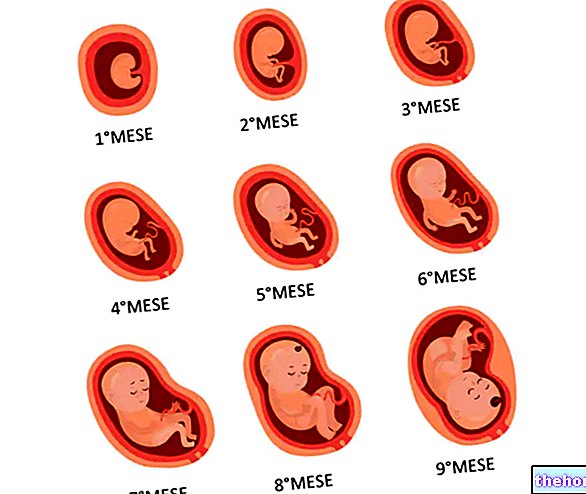

Формирование Плода в Первом Триместре: Важные Этапы